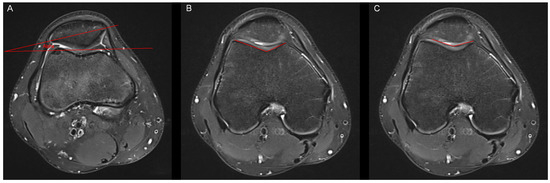

Figure 2. Measurement of the patella tilt angle, the bony sulcus angle and the cartilaginous sulcus angle. (A) In accordance with Grelsamer et al. [10], the patella tilt angle (alpha) was defined as the subtended by a line joining the medial and lateral edges of the patella and a horizontal line measured in the axial slice with the largest mediolateral diameter of the patella. (B) The bony sulcus angle was defined as the angle between the bony medial and lateral facets. (C) The cartilaginous sulcus angle was defined as the angle between the cartilaginous medial and lateral facets.